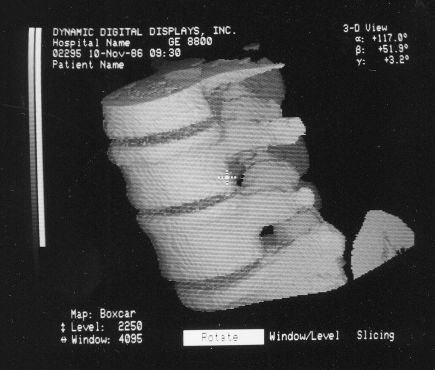

The following VS1 screen-shots were found in a binder along with the VPP photos and hundreds of 35 mm slides of all sorts of stuff:

Voxelscope I Screen Shots. First Row: Multiplanar Reformatting; Second Row: 3-D Shaded Surface

The annotation was generated by the software so no more cutting and pasting. :)

The pair of video monitors was the focus of the booth, displaying sequences of skulls and such from real CT datasets like those in the above photos being rotated, sliced, and diced at reasonably rapid update rates. The instructions for performing the operations were captured and recorded but the actual voxel processing was done in real-time based on the stored program. Thus, no one needed to be constantly spinning the trackball, though that could have been arranged upon request. :) The monitors were up high so visitors couldn't get close enough to see how poor the resolution was. :( :) It is believed that VS1 had a microcode-based pipeline running at 10 MHz so that a 128-cube (2,097,152 voxels) could be manipulated at around 5 images per second. The display was 256x256 pixels on a 60 Hz non-interlaced display - double that of VPP. But object space could be configured to be any arbitrary rectangular prism as long as all the data fit into the voxel processor's memory. The photos, above, are typical of the displays at RSNA.

These photos of the Voxelscope II screen are typical of the types of rendering provided by the system.

Voxelscope II Screen Shots. Combination of 3-D Shaded Surface, Multiplanar Reformatting, and Segmentation